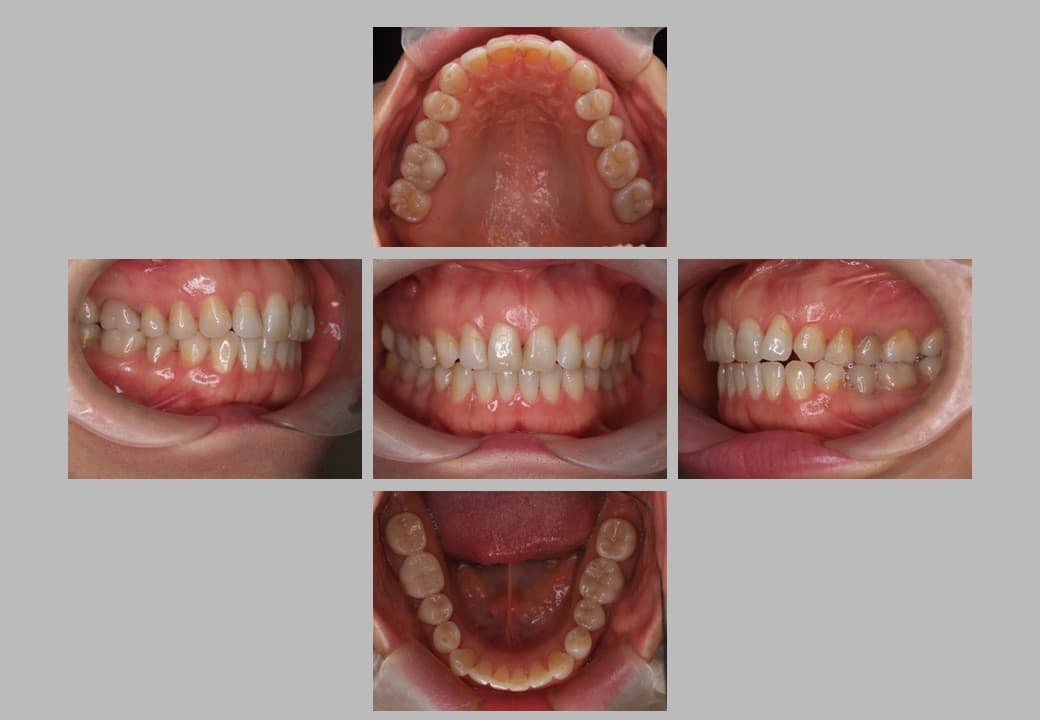

セラミック治療 (メタルフリー治療)の症例紹介①

治療希望:金属の詰め物が取れたセラミックの治療希望

治療内容:根管治療+セラミック治療

治療期間:約6ヶ月

治療後

根管治療+セラミック治療の実施事例です。